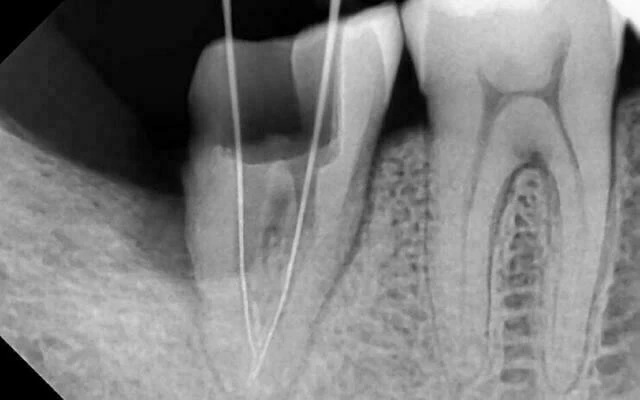

4. Phát hiện có 3 ống tủy (2 gần, 1 xa). Xác định chiều dài làm việc 17mm, sửa soạn tới file kết thúc Niti 30.04. Bôi trơn file mỗi lần đi file bằng Glyde (Densply)

6. Hàn tủy bằng côn gutta percha F3 và cortisomol bằng phương pháp lèn ngang nguội. Kiểm tra lại độ khít sát bằng phim âm bản.